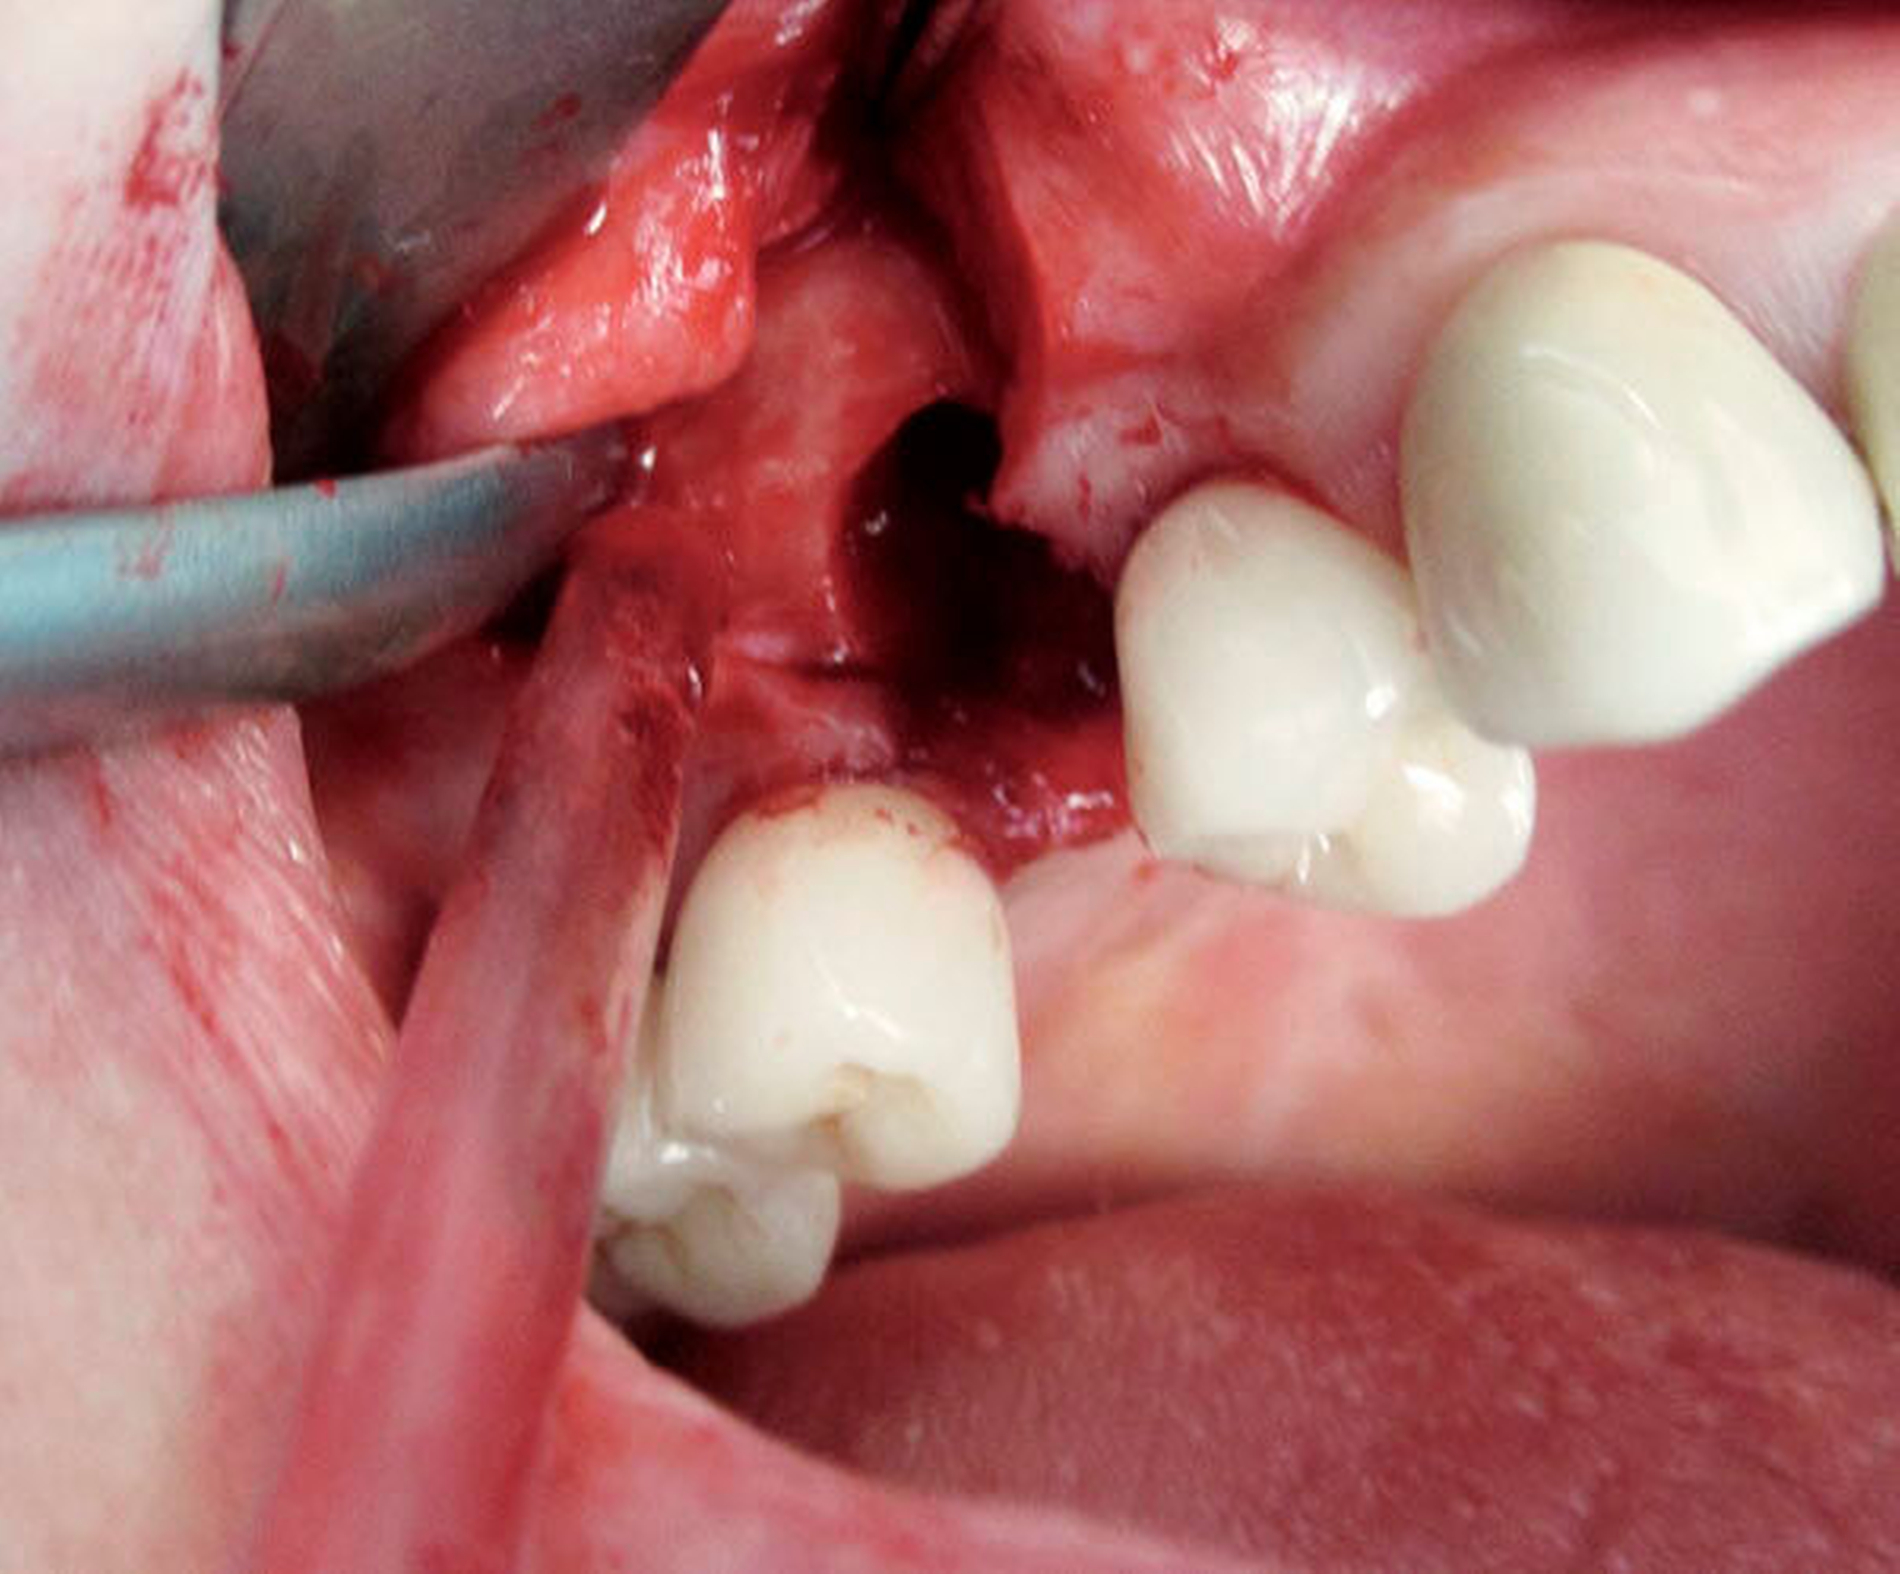

In beiden Fällen erfolgte die Entfernung des Zahnes/Implantats aus der Kieferhöhle (Abbildungen 4 und 5).

Der luxierte Zahn konnte mittels Extraktionszange gefasst werden. Es bestand eine Mund-Antrum-Verbindung, die plastisch verschlossen wurde (Abbildungen 6 und 7). Postoperativ war die Patientin weiterhin beschwerdefrei.